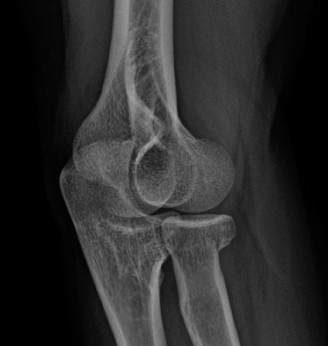

A 20-year-old female presents to the office complaining of pain and swelling in the elbow. She denies any rec…